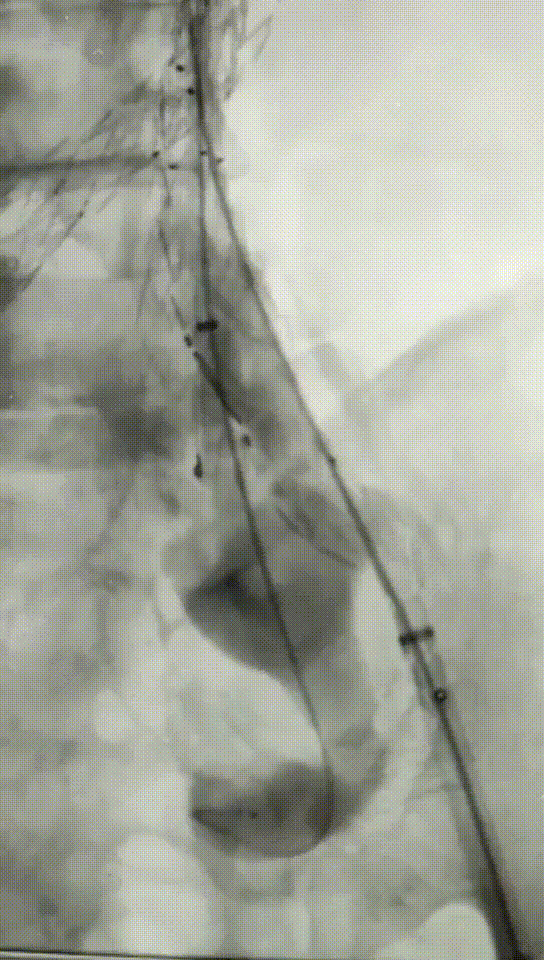

手术过程:根据患者及家属要求保双侧髂内,遂计划双侧髂内重建,右侧优先,左侧髂内情况尝试开通。手术中,先进行造影和翻山建立通路。

造影

翻山建立通路